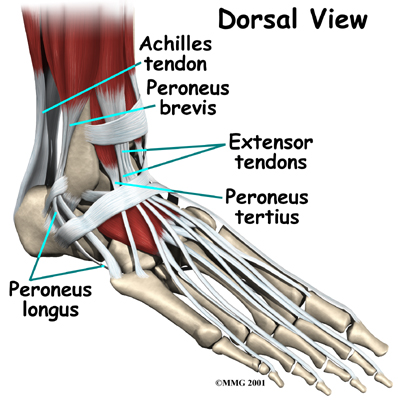

Ligaments on both sides of the ankle joint help hold the bones together. Many tendons cross the ankle to move the ankle and the toes. (Ligaments connect bone to bone, while tendons connect muscle to bone.)

Tendons

The large Achilles tendon at the back of the ankle is the most powerful tendon in the foot. It connects the calf muscles to the heel bone and gives the foot the power for walking, running, and jumping.